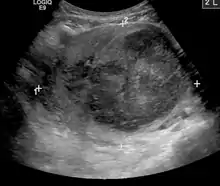

The presence of a uterine fibroid versus an adnexal tumor is made. Fibroids can be mistaken for ovarian neoplasms. An uncommon tumor which may be mistaken for a fibroid is Sarcoma botryoides. It is more common in children and adolescents. Like a fibroid, it can also protrude from the vagina and is distinguished from fibroids.[7] While palpation used in a pelvic examination can typically identify the presence of larger fibroids, gynecologic ultrasonography (ultrasound) has evolved as the standard tool to evaluate the uterus for fibroids. Sonography will depict the fibroids as focal masses with a heterogeneous texture, which usually cause shadowing of the ultrasound beam. The location can be determined and dimensions of the lesion measured. Also, magnetic resonance imaging (MRI) can be used to define the depiction of the size and location of the fibroids within the uterus.

A very large (9 cm) fibroid of the uterus which is causing pelvic congestion syndrome as seen on ultrasound